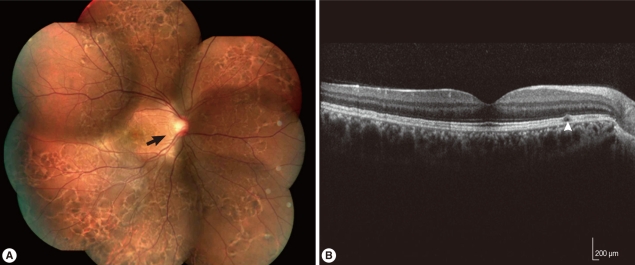

Two years later, he visited our clinic again for an ophthalmic examination. Visual acuity was 20/20 in both eyes, hypopigmented linear lesions were observed across the whole fundus in the right eye on fundus examination, and subretinal tracks were observed on optical coherence tomography (Fig. 2). Because subretinal tracks can be found in several different types of parasitic infections and thus are not diagnostically specific. Based on the history and clinical infection of the patient, we suspected the infection of Gnathostoma spp. and performed western blot analysis. Western blot assay was carried out with the soluble lysate of G. nipponicum. In brief, the soluble lysate of G. nipponicum was separated by 10% SDS-PAGE and transferred to nitrocellulose membrane. The membrane was cut into strips and blocked with PBS supplemented with 0.05% Tween 20 (PBST, pH 7.4) and 3% skim milk for 1 hr at room temperature. The strips were then incubated with a 1:50 or 1:100 diluted positive serum collected from a patient with gnathostomiasis, a serum from this patients, and a serum of normal healthy person for 2 hr [9]. After several washes with PBST, the strips were incubated with 1:1,000 diluted horseradish peroxidase-conjugated anti-human IgG (Sigma, St. Louis, Illinois, USA) and the immunoreactive bands were visualized with 4-chloro-1-naphthol (Sigma). Several immunoreactive bands ranged from 50-100 kDa, which suggested positive antibody responses against the antigens of the parasite, were identified (Fig. 3). Other serologic tests with molecular band for antigens from Angiostrongylus, Paragonimus, Toxocara, and other parasitic origins were performed. Serologic results for other parasites were negative. Collectively, we made a diagnosis of intraocular gnathostomiasis based on the history of ingesting raw wild boar meat and lobster in an endemic area of gnathostomiasis, as well as the mild eosinophilia and positive western blot assay result.

In general, intraocular parasitic infections reported to date include gnathostomiasis, toxoplasmosis, toxocariasis, Acanthamoeba keratitis, cysticercosis, onchocerciasis, and ophthalmomyiasis [10,11]. Symptoms of intraocular gnathostomiasis include lid swelling, iritis, iris atrophy, iris hole, retinal scarring (subretinal tracks), and retinal detachment. In particular, Biswas et al. [7] found that subretinal tracks were multiple yellow linear tracks, which suggested the migratory path of the subretinal parasite, and were seen subretinally in the posterior pole and in the periphery, but no parasite was actually seen.

Finding subretinal tracks does not necessarily lead to the conclusive diagnosis of parasitic disease. Subretinal tracks involving choroidal macrovessels were observed on fundus examination in 1 reported case [39]. If subretinal tracks are found, a parasitic disease is suspected, and in our case, choroidal macrovessels and other retinal vascular diseases are excluded based on the fluorescein angiographic and optical coherence tomographic findings. In addition, the travel history of the patient to the endemic area was helpful in leading to the diagnosis of a parasitic disease. Fundus findings of the subretinal tracks, however, were not diagnostically specific and mild eosinophilia in the blood count alone was not sufficient for a definitive diagnosis. We suspected the patient as having gnathostomiasis because he stayed in Vietnam for 1 week, consumed raw wild boar meat and lobster there, and the eye was involved. A serologic test for Gnathostoma antigen was conducted, followed by other serologic tests for Angiostrongylus, Paragonimus, Toxocara, and other parasites, in order to find cross reactivity with gnathostomiasis [4,15]. The serologic tests for other parasites were negative and western blot assay was used to examine the reactivity of the patient's serum to Gnathostoma antigen compared with a positive reference serum for gnathostomiasis. The results revealed 4 reactive bands which were identical in the 2 samples.